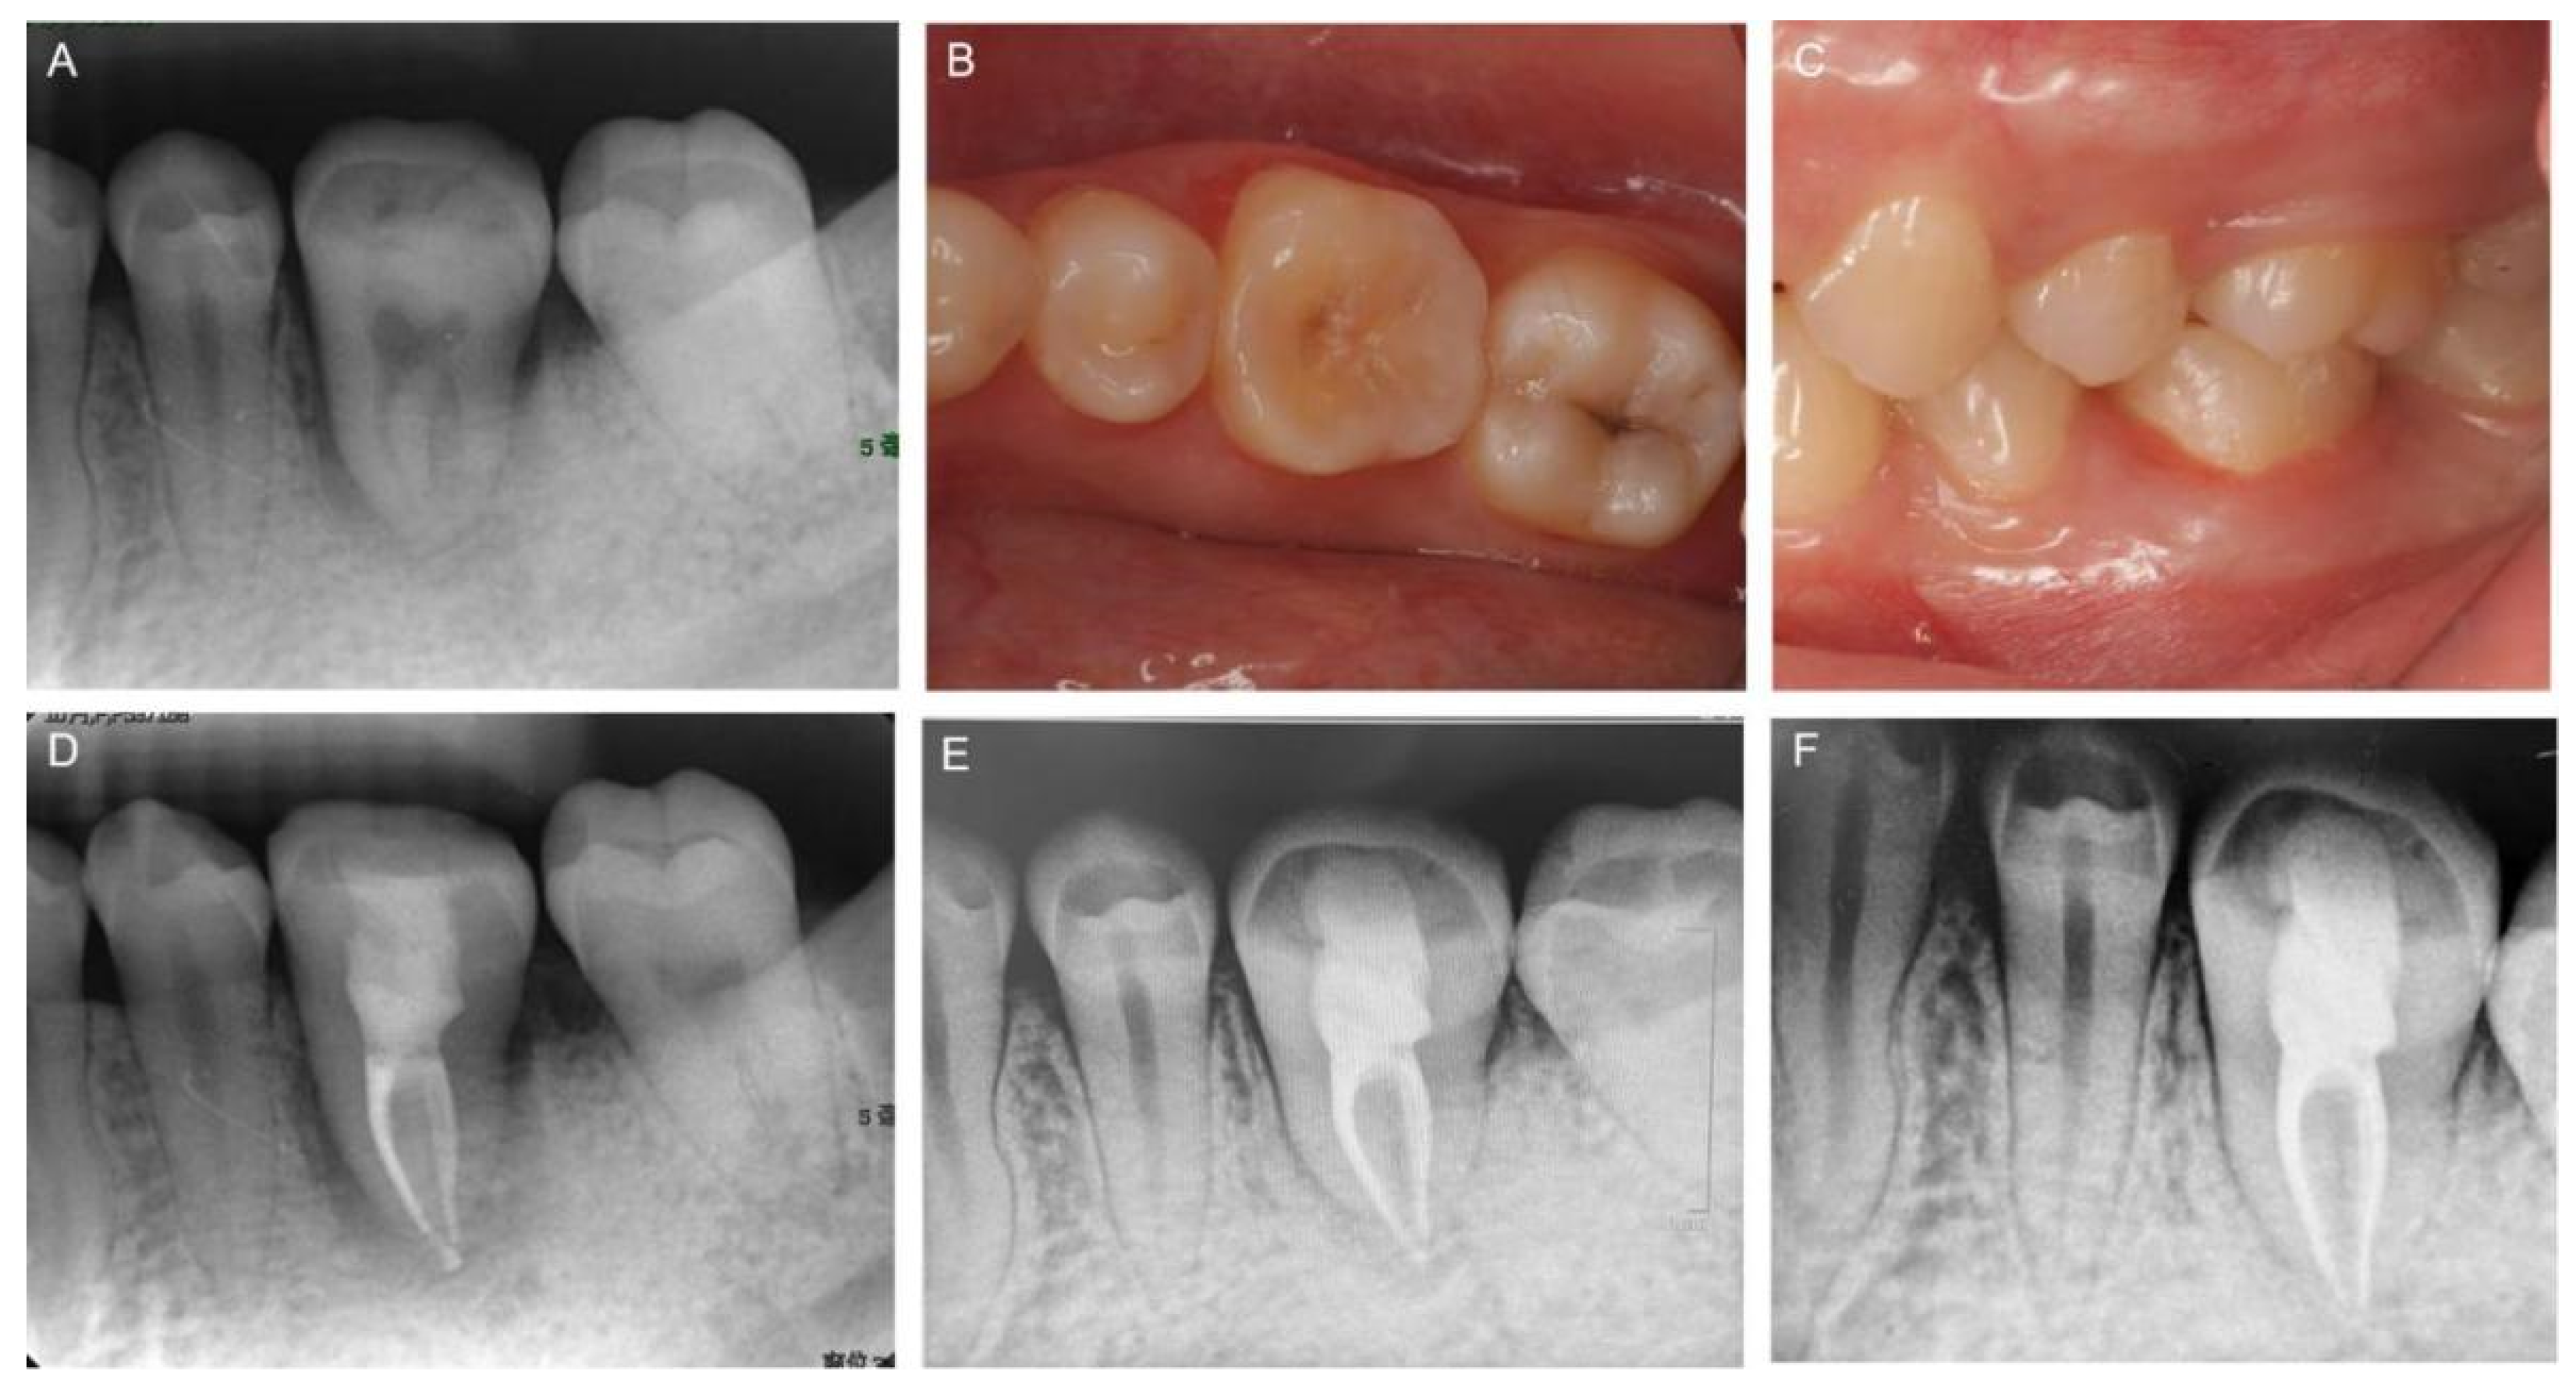

2. Case Report

3. Results